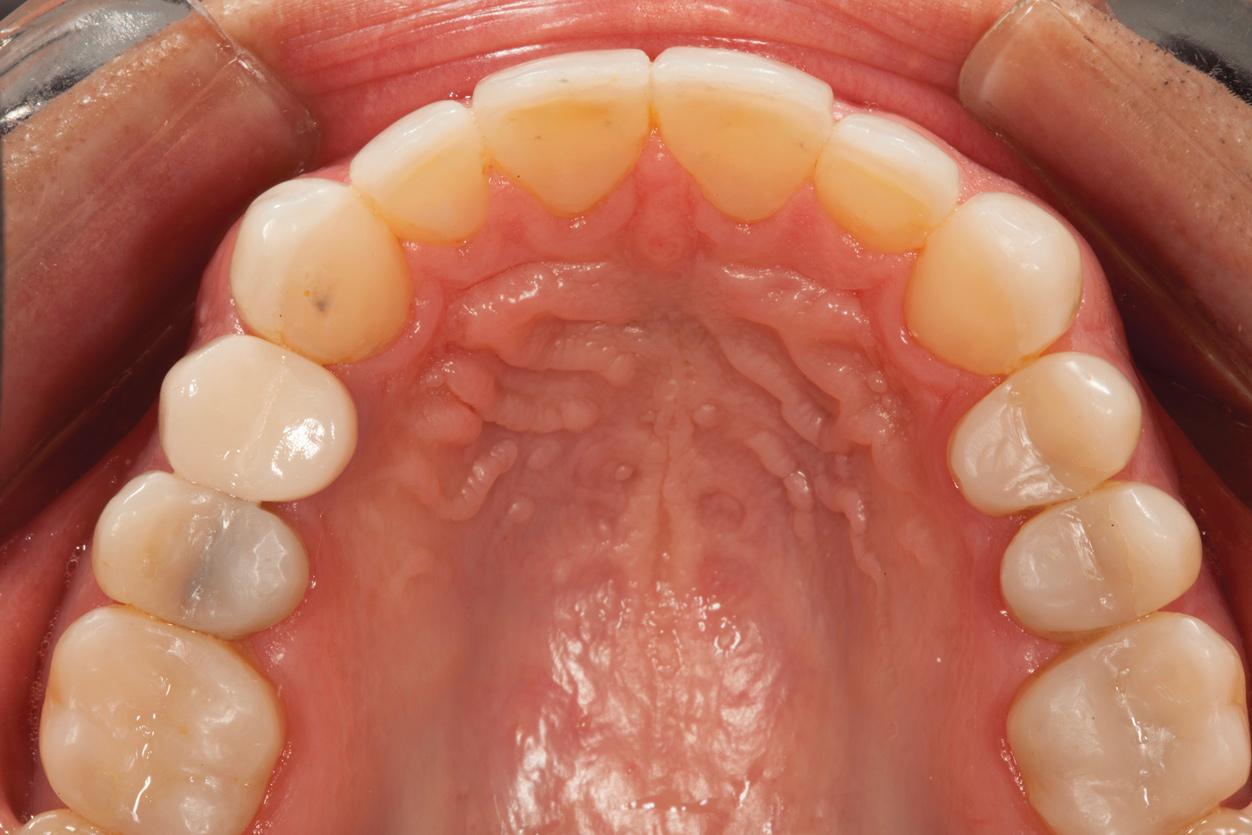

Following caries treatment and tooth preparation (Figure 6), teeth Nos. 4 through 13 were restored with direct composite veneers in stages (Figure 7 through Figure 9). Using a hybrid composite for the lingual shelf and dentin layer provides wear resistance and strength for the restoration.14,15 (The lowest wear rates for restorations and the opposing dentition occur with metal alloys, machined ceramics, and microfilled hybrid resin composites. Any adjusted and unpolished porcelain surface would elicit the most wear on the opposing teeth.11)After the composite veneers were finalized, a monolithic lithium disilicate crown was placed on tooth No. 12 during a subsequent appointment, and occlusal equilibration was carried out. Final photographs were taken a couple of weeks later (Figure 10 through Figure 14).

Fig 10. Postoperative smile photograph.

Figure 10

Fig 12. Postoperative upper anterior view and occlusal views of the upper and lower arches.

Figure 12

Fig 14. Digital smile design software enables parameters of interim prosthesis to be facially generated; (Fig 12) front view, (Fig 13) occlusal view, (Fig 14) 12 o’clock view.

Figure 14